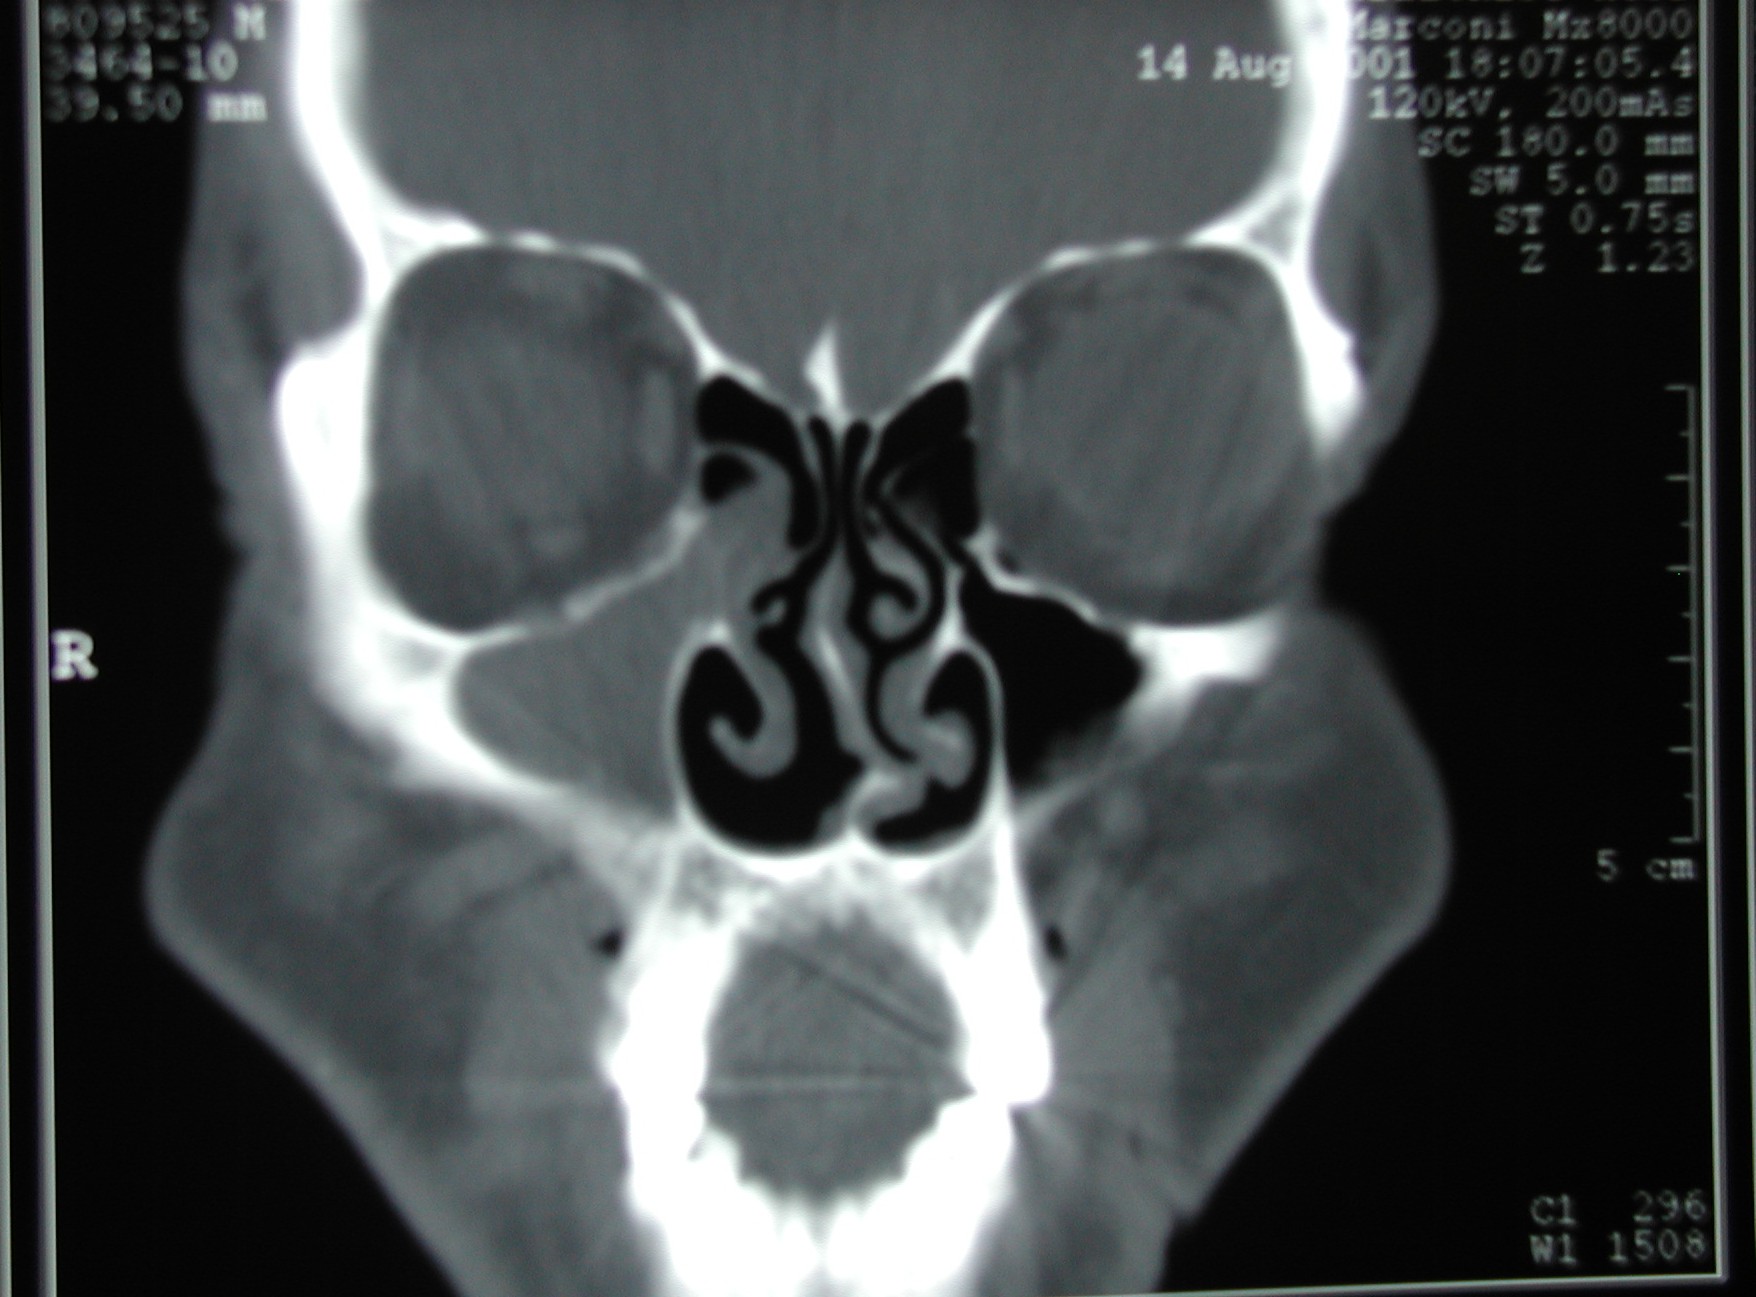

This patient has a unique CT: unilateral sinus disease.  This could have been due to a tumor, foreign body, or fungal disease.